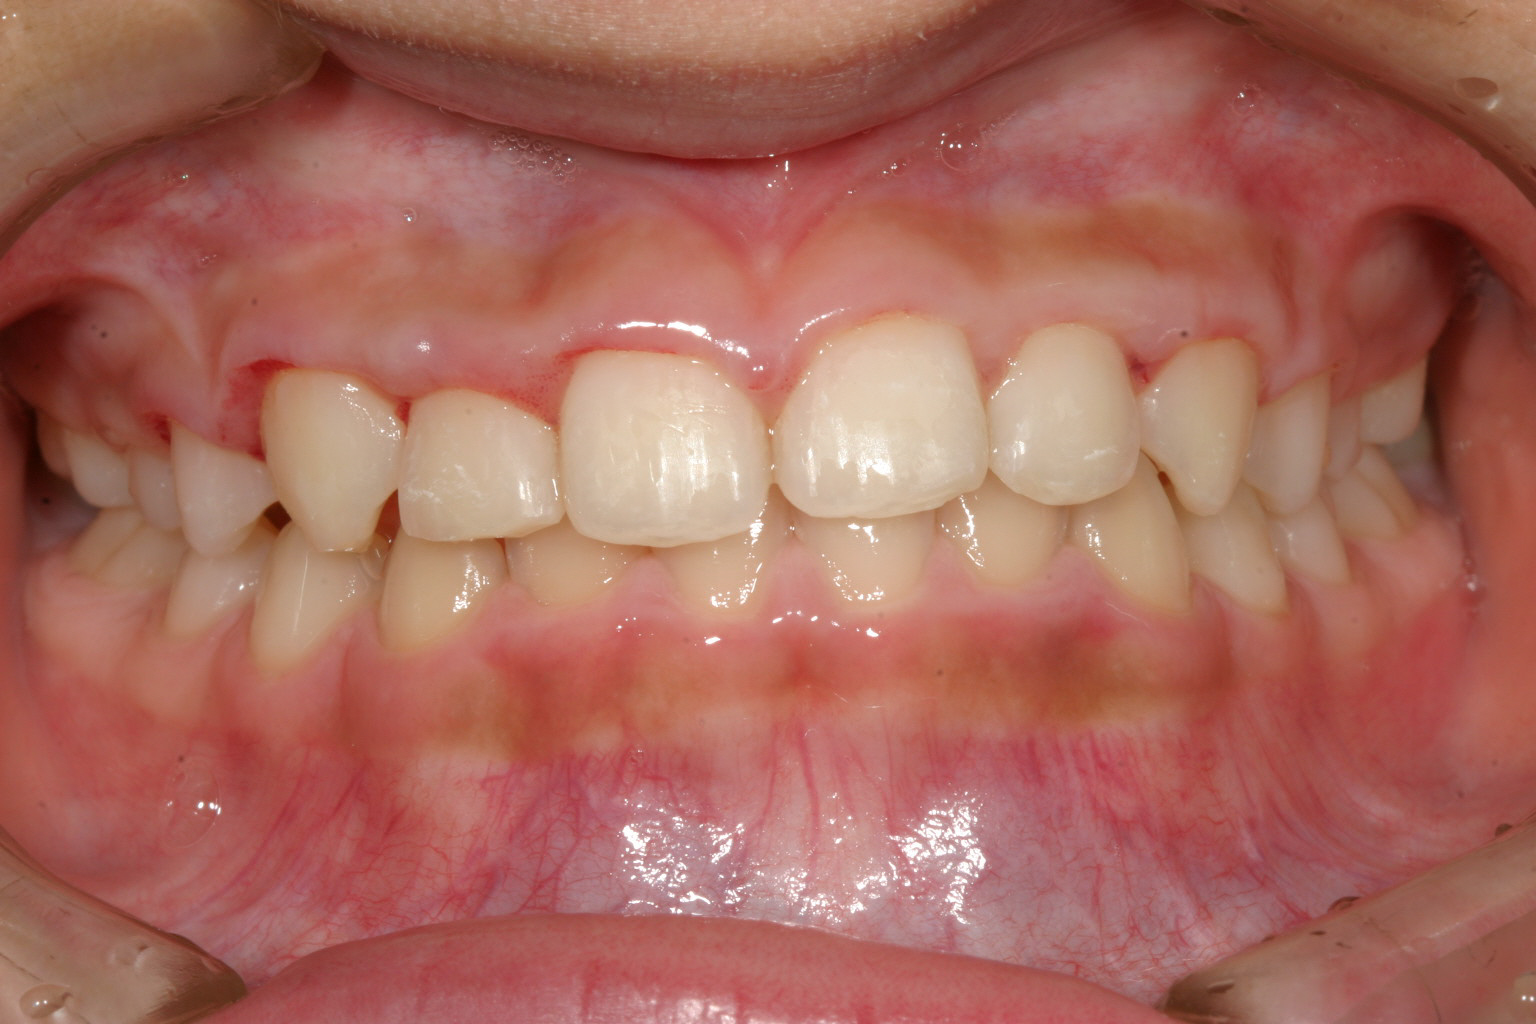

2か月後の正面観です。

初診より4ヵ月で終了です。

初診より僅か4カ月で受け口終了しました。